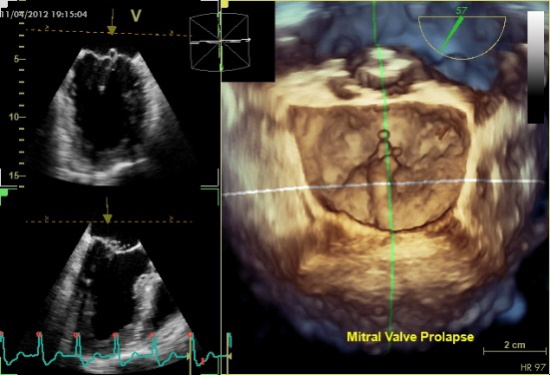

图11四腔心切面显示二尖瓣后叶P2区脱垂

图12 5腔心切面显示二尖瓣前叶A1区脱垂

图13食管中段左室长轴切面显示二尖瓣后叶P2区腱索断裂并脱垂

图14经胃底基底段短轴切面。示二尖瓣前后叶,P3区位于“扇形”的顶点

二尖瓣环是一个空间立体环,形状近似“马鞍形”,美国超声心动图协会指南建议应用四腔心切面于舒张中期测量二尖瓣环径,并应用圆形公式来计算瓣环面积,但是这种计算方法简化了瓣环的复杂结构。本文推荐应用左室长轴和交界区切面测量二尖瓣瓣环径,计算二尖瓣环面积。左室长轴测量二尖瓣环径时,应仔细观察二尖瓣瓣叶的附着点。而这种相互垂直的两个平面在多平面或三维超声(图15,16)上很容易得到。

图15正常二尖瓣2个相互垂直平面 图16二尖瓣P2脱垂2个相互垂直平面

应用经食管实时三维超声心动图评价二尖瓣对以下情况很有帮助:确定病变的部位和范围;确定瓣膜功能异常的机制和程度;与外科医生直接交流超声检查结果,有利于手术计划的制定。另外,实时三维超声有利于判断累及多个小叶的脱垂,对于交界区的病变和瓣叶裂更具有帮助。